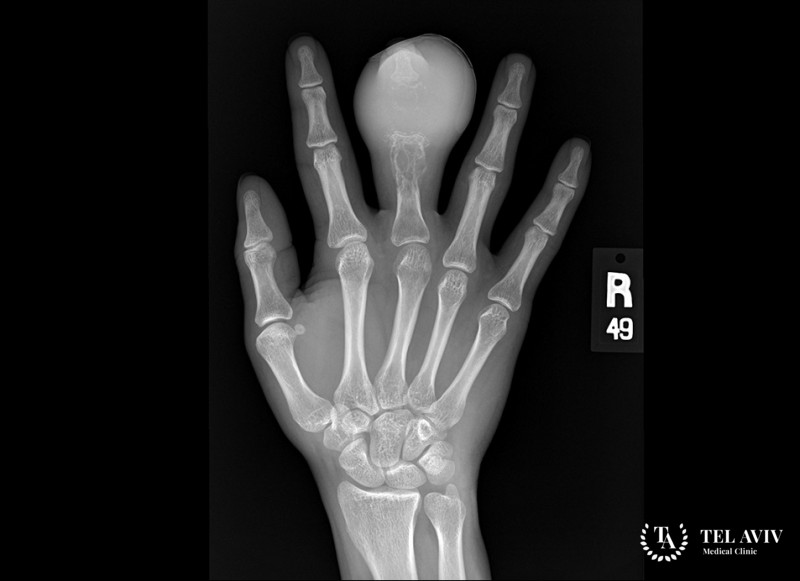

- Рентген;